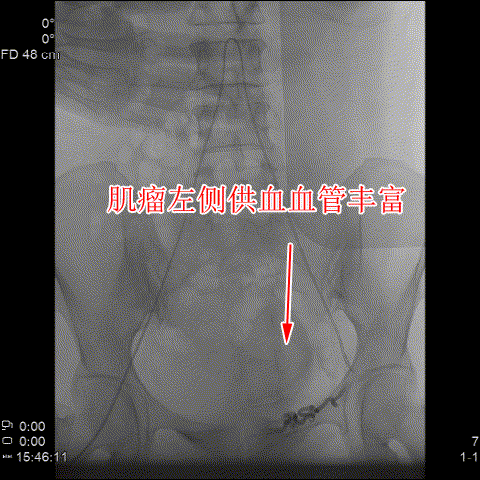

△術前造影可見肌瘤左右側的供血豐富。

随後,李旭丹主任與胡志華主任聯手爲患者實施手術,通過患者股動脈穿刺,置入微導絲、導管,經動脈自然腔道将導管送達左右側髂總動脈進行造影,可見肌瘤供血血管,随後利用微導管将特制栓塞材料送達子宮動脈進行栓塞。造影顯示子宮肌瘤供血已被掐斷,順利完成手術。